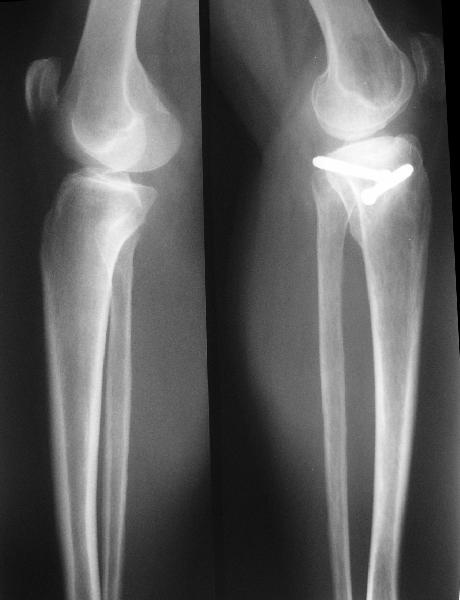

В отделение поступила  пациентка из области, 68 лет.

Травму получила год назад, находилась на лечении  в ЦРБ по поводу перелома внутреннего мыщелка большеберцовой кости, была вот так прооперирована.

На сегодняшний момент беспокоят боли в области коленного сустава при ходьбе, движения ограничены, от 180 до 100.